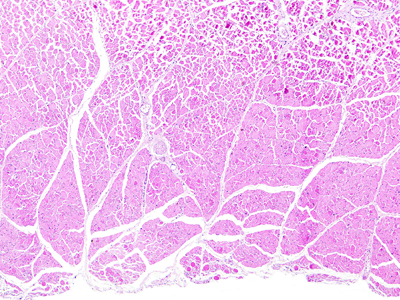

Die Psoriasis ist eine sehr belastende Erkrankung mit hoher volkswirtschaftlicher Bedeutung und häufig lebenslangen Krankheitsverläufen. Die Forschung versucht das Spektrum der Therapiemöglichkeiten ständig zu erweitern um Psoriasis-Patienten einen stabilen guten Hautzustand und eine Verbesserung der Lebensqualität zu ermöglichen. Wir führen eine Arzneimittelstudie mit einem neu entwickelten noch nicht zugelassenen Medikament durch.